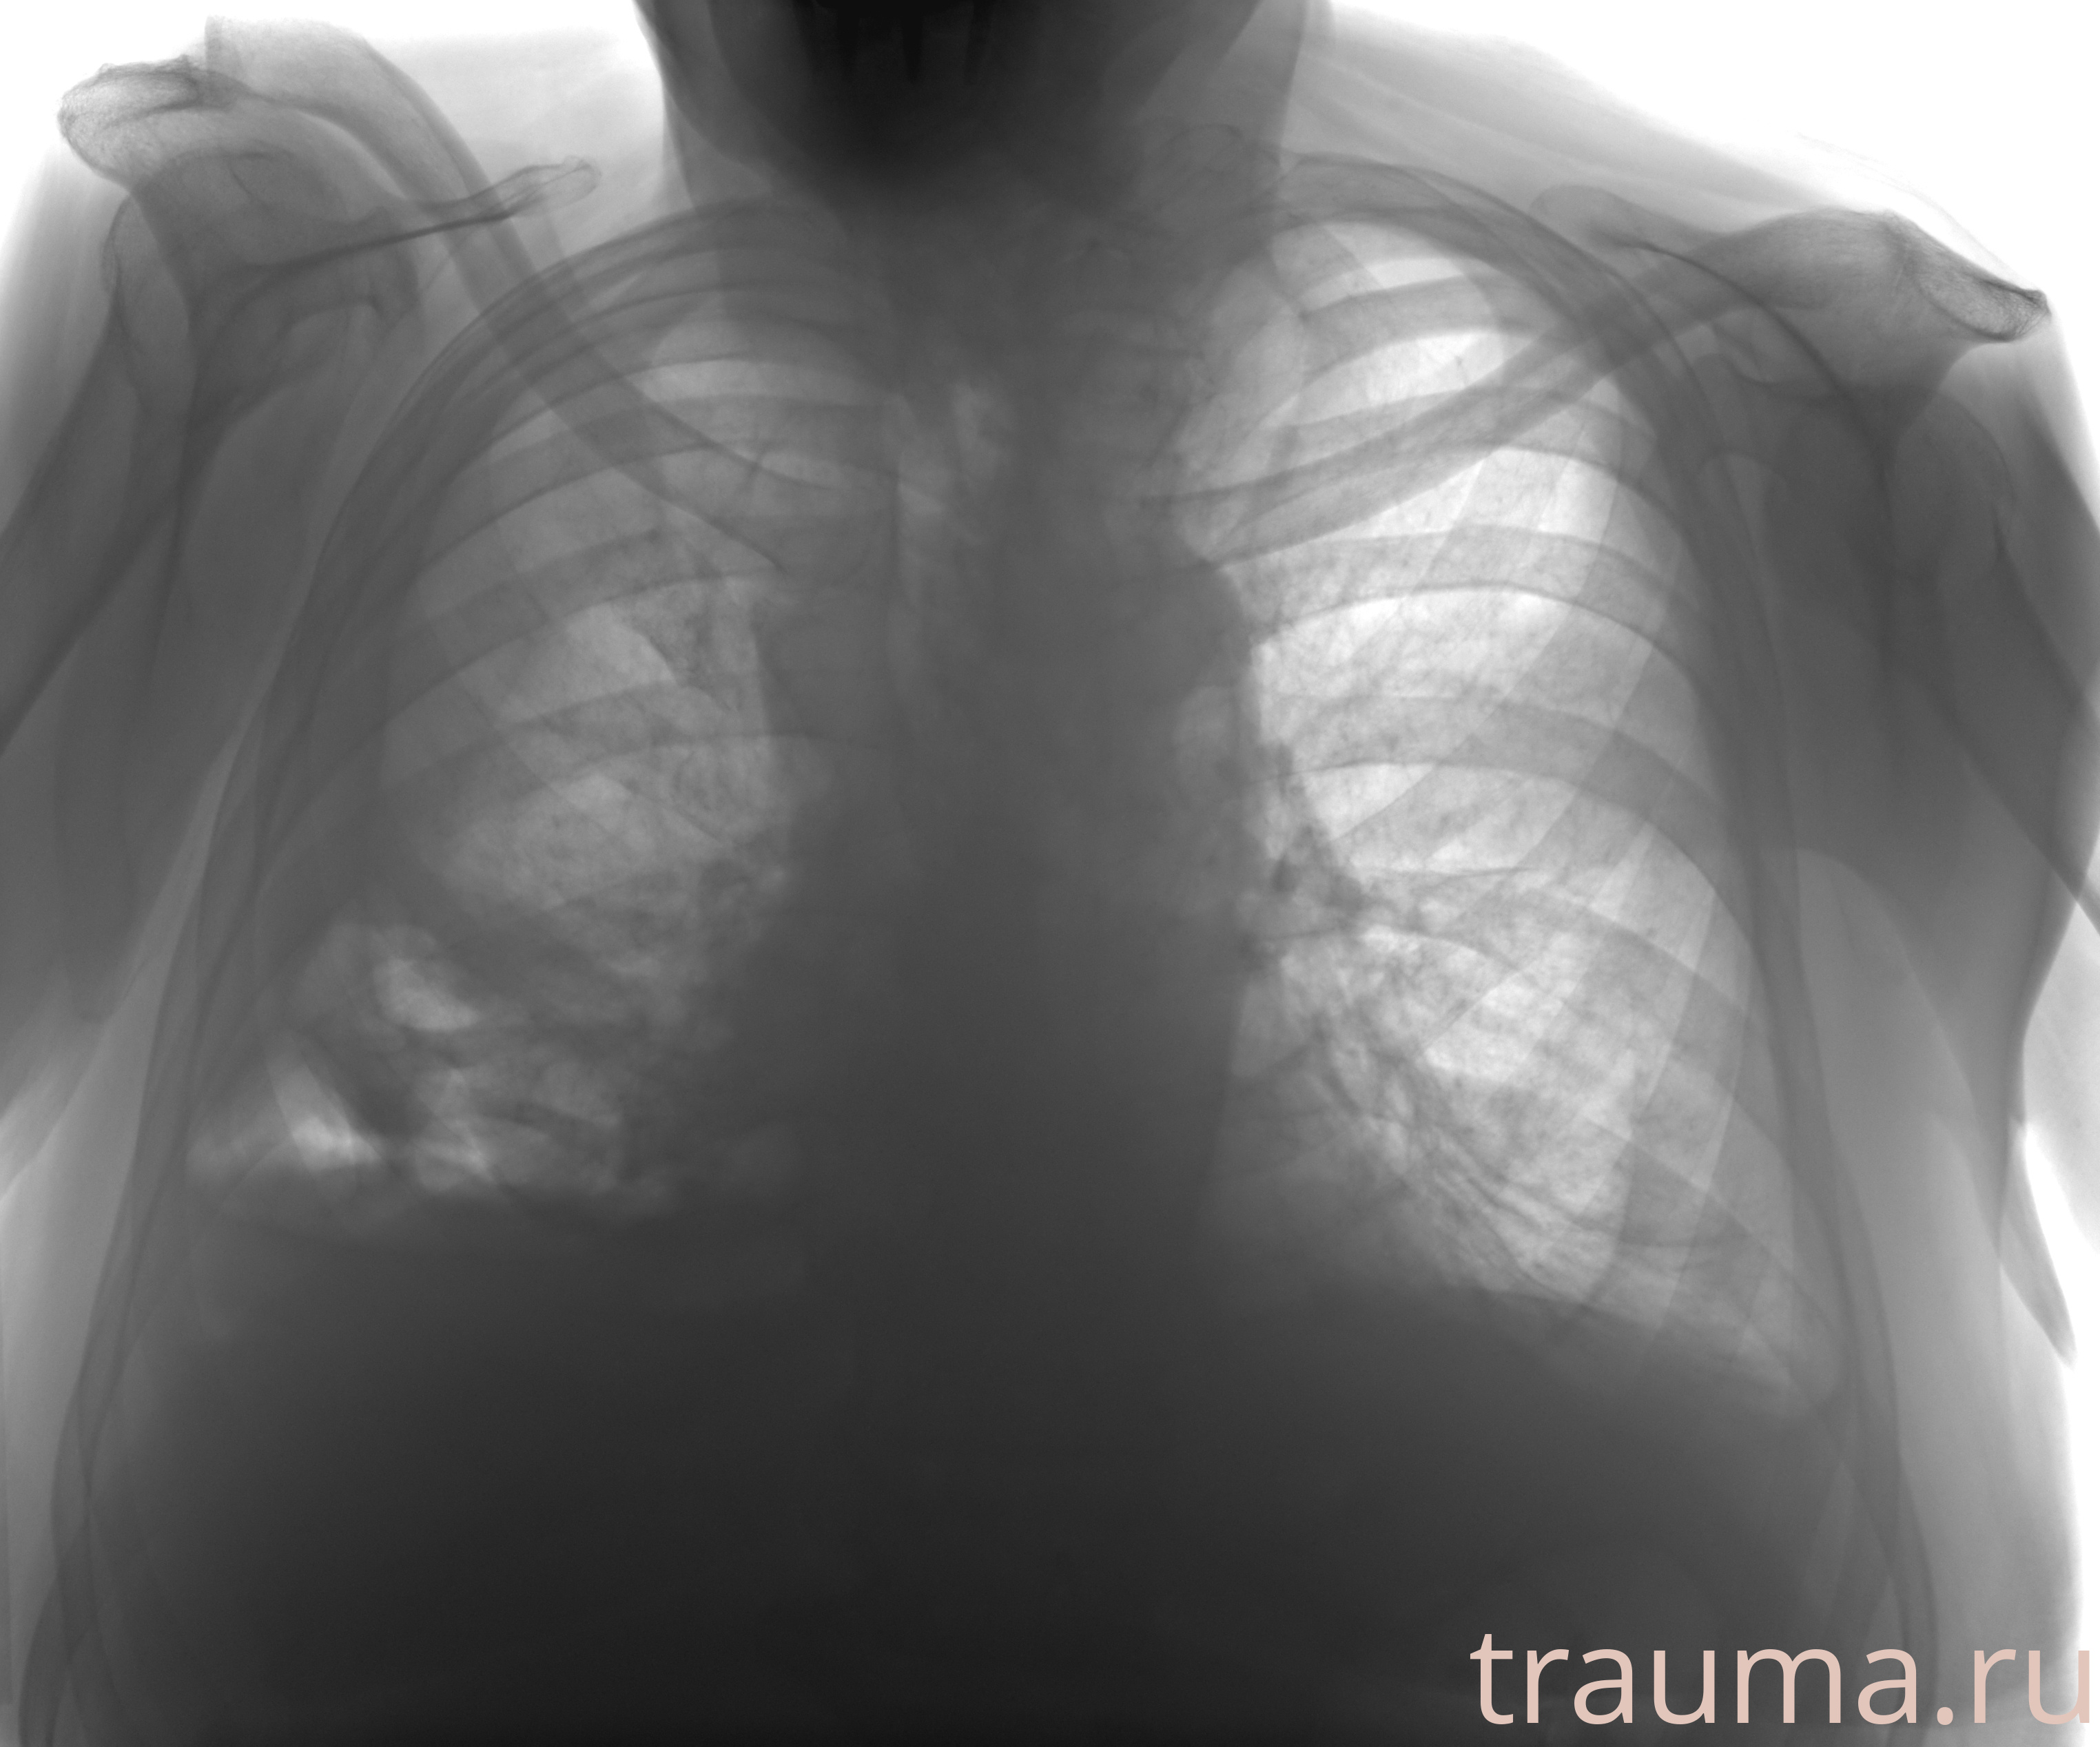

Рентген на дому: по вашему адресу приезжает врач-рентгенолог, травматолог-ортопед с мобильным рентгеновским аппаратом, проводит диагностику травмы или заболевания, делает необходимые рентгенограммы, дает рекомендации по дальнейшему лечению. Получить качественные снимки в домашних условиях возможно благодаря уникальной методике, разработанной МосРентген Центром для института  Склифосовского